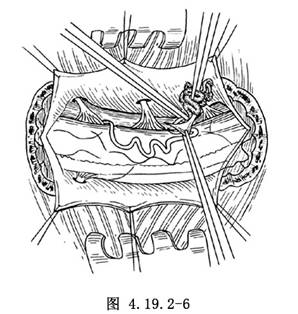

4.切開硬脊膜,將硬脊膜內已動脈化的位於硬脊膜和脊髓之間的粗大引流靜脈,以雙極電凝閉塞並予以切除(圖4.19.2-6)。